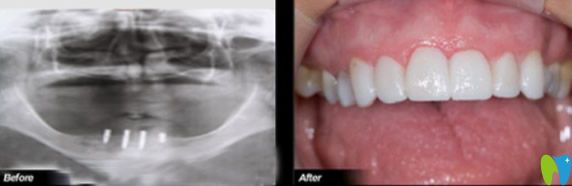

深圳歡樂口腔堅持口腔治療、四手規(guī)范操作、“一人一機(jī)”無菌消毒的標(biāo)準(zhǔn)化醫(yī)療規(guī)范,廣泛應(yīng)用3D打印、數(shù)字引導(dǎo)種植牙、顯微鏡下超薄美容牙、口腔數(shù)字化CT掃描等主流的全數(shù)字化新技術(shù)、新方法,達(dá)到了良好的治療,并得到了患者的普遍贊譽(yù)。下圖是真人種植牙,大家覺得深圳歡樂口腔怎么樣?